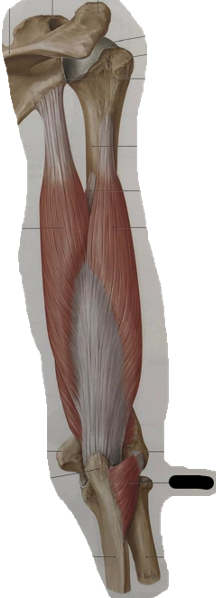

anatomie elleboog (spieren) (learn mode)

m. biceps brachii (caput longum/breve) (flexie, supinatie)

m. brachialis (flexie)

m. brachioradialis (flexie, supinatie, pronatie)

mm. extensores carpi radialis longus en brevis (flexie)

m. pronator teres (flexie, pronatie)

m. flexor digitorum superficialis (flexie)

m. palmaris longus (flexie)

m. triceps brachii (extensie)

m. anconeus (extensie)